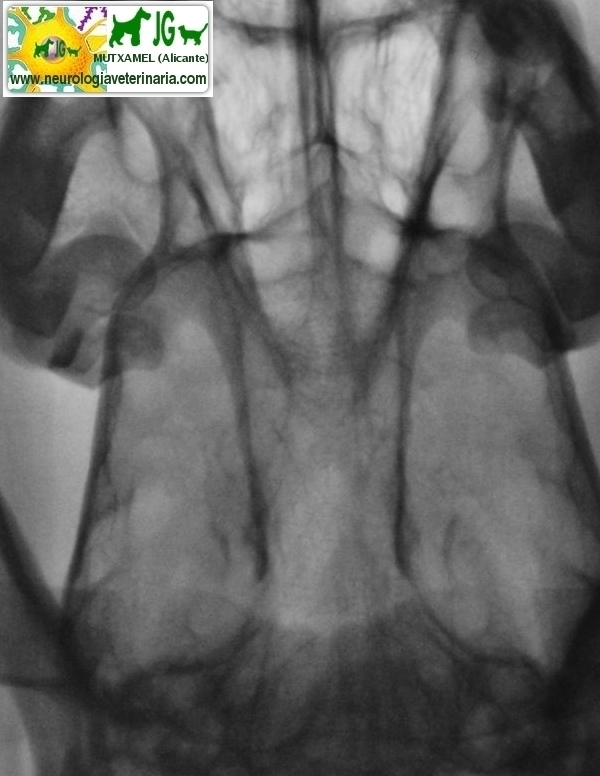

Radiografía simple (sin contrastes) | |||||||||

Radiografía digitalizada de cachorro de Siberian Husky con severo trauma craneal |